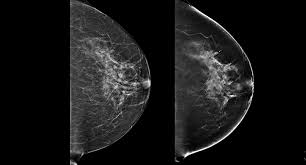

What Does Breast Cancer Look Like On A 3D Mammogram / Mammogram Images Normal And Abnormal - Treatment typically involves some type of surgery and depends upon the staging of the.. The tumor cells don't stay within the clear borders of the mass, but instead invade the nearby breast tissue. The look of breast cancer on a mammogram a tumor or lump will appear as a focused white area on the mammogram. Tumors may be benign or cancerous. Rather than an image that is formed from pictures taken from top to bottom and side to side like a. 3d mammography, or breast tomosynthesis, is a relatively new breast imaging procedure approved by the u.s.

Dense breast tissue appears solid. Essentially, mammograms turn a 3d object into a 2d object. Finding breast lumps and seeing change in the size and shape. Ultimately, the news is good: A number of studies have found that 3d mammograms find more cancers than traditional 2d mammograms and also reduce the number of false positives. A mammogram can show breast changes such as calcifications, masses, or other symptoms that might be cancer. Calcifications are calcium deposits within the breast tissue and they look like small white spots. Digital breast tomosynthesis (tomo), also known as 3d mammography, is a revolutionary new screening and diagnostic breast imaging tool to improve the early detection of breast cancer. American cancer society, 9 oct 2017. Ultrasound characterization of breast masses. indian journal of radiology and imaging. However, when the breast is compressed from top to bottom, the tissue in the upper breast can overlap tissue in the lower breast. Any area that does not look like normal tissue is a possible cause for concern. It appears to be developing in a concentric pattern.

What does breast cancer look like on a mammogram? Screening mammograms have been used since the 1980s. On mammograms, dense breast tissue looks white. Bright spots on a mammogram that look like potential tumors could turn out to be overlapping tissues or a blood vessel folding over on itself, friedewald said. The outer edges of these cells look fuzzy or spiky (called spiculated). Moose & doc breast cancer, 21 may 2018. It is also an anatomic test, which means cancer is detected based on changes in how the breast anatomy looks. Food and drug administration in 2011. After a mammogram that didn't show anything, and a sonogram that found the lump, i was diagnosed with stage 2 breast cancer. Treatment typically involves some type of surgery and depends upon the staging of the. What does breast cancer look like on a mammogram? It appears to be developing in a concentric pattern. A mammogram can show breast changes such as calcifications, masses, or other symptoms that might be cancer.